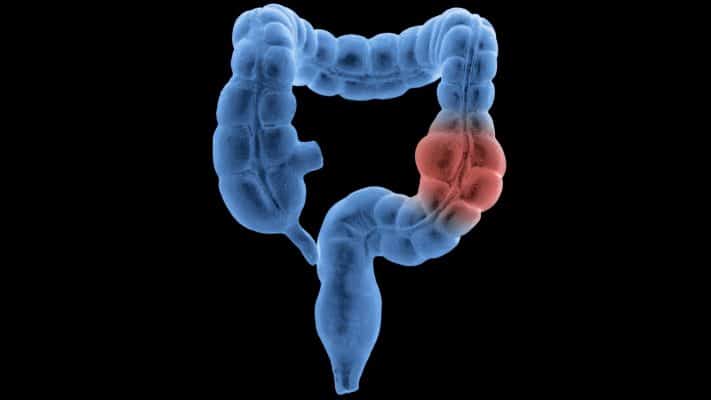

«Δεν είναι μόνο καρκίνοι στο οικογενειακό σας ιστορικό, είναι και πολύποδες υψηλού κινδύνου», είπε. Εάν τα στενά μέλη της οικογένειας είχαν περισσότερους από τρεις πολύποδες ή μεγάλους πολύποδες, θα πληροίτε τις προϋποθέσεις για πρώιμη κολονοσκόπηση, είπε ο Ricci. Οι πολύποδες μπορούν να μετατραπούν σε καρκίνο αν δεν αφαιρεθούν. Οι αλλαγές στις συνήθειες του εντέρου και η αιμορραγία — συμπτώματα καρκίνου του παχέος εντέρου — είναι λόγοι που πρέπει να αξιολογηθούν από τον γαστρεντερολόγο σας. «Όταν έχεις συμπτωματικό καρκίνο, συνήθως είναι πιο μακριά», είπε ο Ricci.